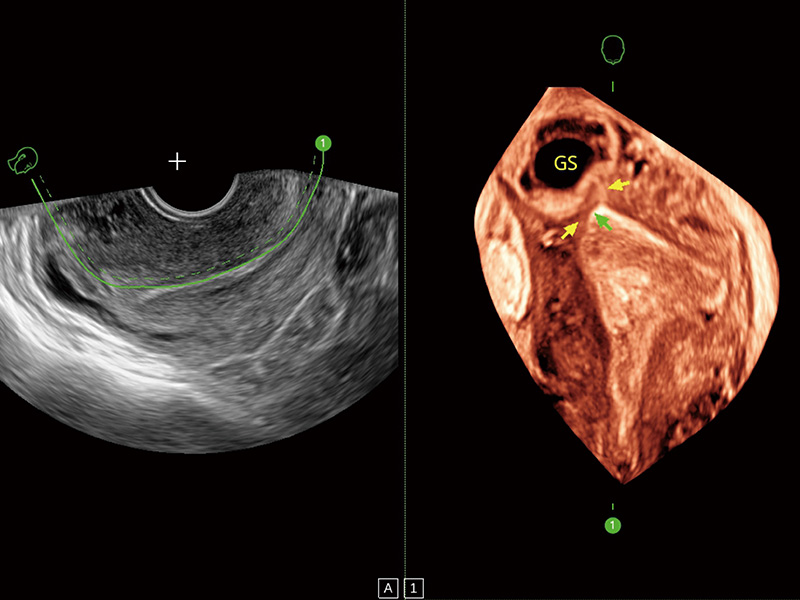

临床图

中央型宫腔粘连

输卵管间质部妊娠